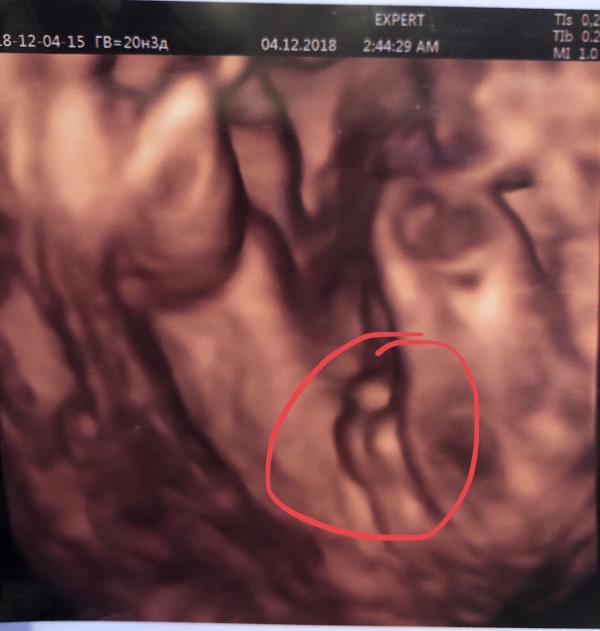

У нас будет МАЛЬЧИК ! 🥰🎩🏀🏆🚗

Даа) кулачки воинственно держит! Ещё родителей ругал указательным пальчиком, за то, что думали, что в животике девочка😁 Спасибо большое 😊